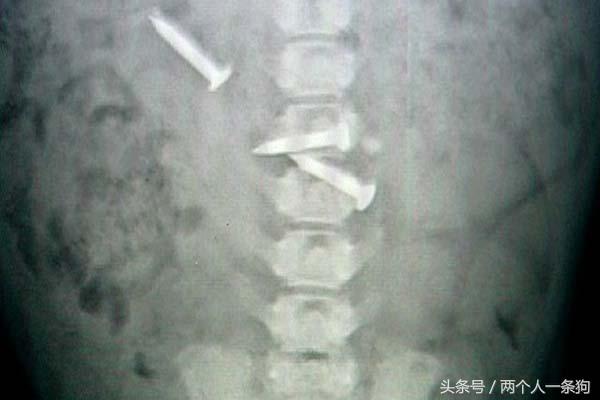

女子把这些拿下来之后,突然想到,为什么磁铁会吸在肚子上,再一试果然又吸住了,这可把她吓了一跳,感觉带着法斗去医院,医生拿出磁铁试了试,说法斗估计是吞了金属到肚子里,拍完X光片确定之后立即进行手术,从法斗的肚子里取出了好几个钉子,还有瓶盖,医生说这应该是刚咽进去,如果通过胃再进入肠道,那可能会有生命危险。